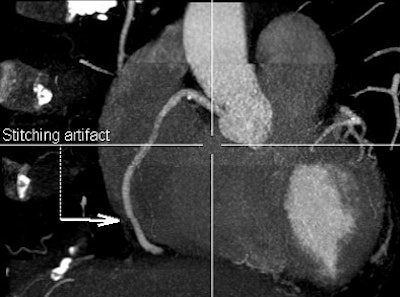

![]() |

| Owing to the need to acquire cardiac images over several heartbeats, coronary CT angiography at 64-detector-row CT produces more artifacts than 320-detector-row CT, which acquires the entire cardiac volume in a single beat, or two beats for a longer triple-rule-out study. Above, 320 image acquired over two heartbeats has a single stitching artifact (arrow), while the 64 image below contains four important artifacts, only one of which is labeled with an arrow. Can you find the rest? Images courtesy of Dr. Melissa Daubert and Dr. Michael Poon. |